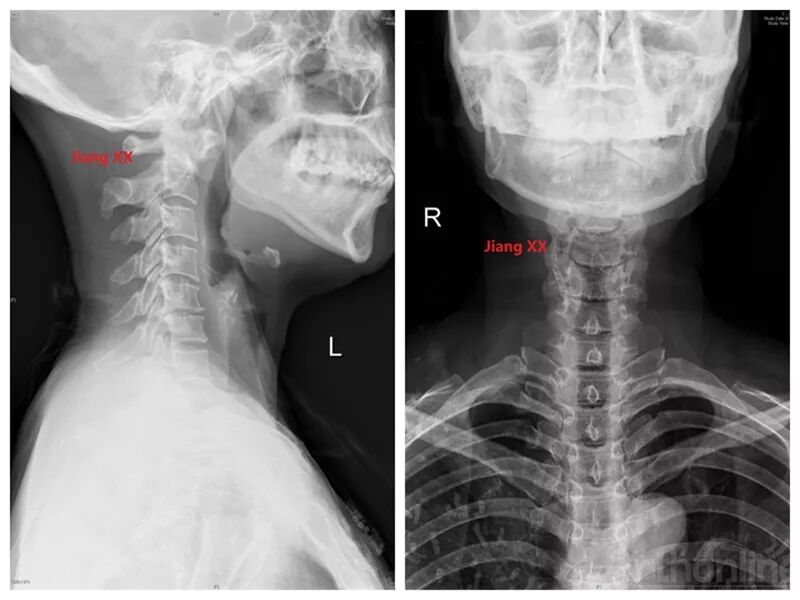

病例一:患者女性,49岁,因颈部活动受限4月入院,诊断为寰枢椎脱位,颅底

寰枢椎脱位合并阻滞椎一例. 术者:孙晓立 助手:刘宏雷

寰枢椎脱位